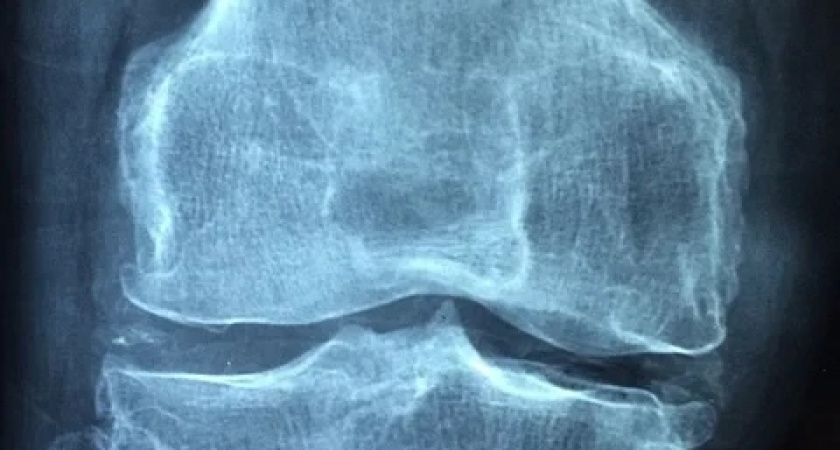

Определенный вид боли в ногах может сигнализировать о высоком уровне холестерина в крови, который провоцирует воспаление и приводит к изменению структуры сухожилий.

Ахиллово сухожилие расположено на задней части ноги, оно является самым мощным в теле человека. Воспалительные процессы в нем могут возникнуть из-за травм или чрезмерных нагрузок. Однако плохой холестерин тоже может стать причиной воспаления ахиллова сухожилия, пишет Daily Express со ссылкой на экспертов Alliance Foot and Ankle Specialists.

Боль в ногах при подъеме на лестницу, слабость в районе голени, болевые ощущения и отеки пяток свидетельствуют об ослаблении сухожилий из-за структурных изменений, вызванных высоким холестерином. При появлении этих симптомов необходимо обратиться к врачу и сдать анализы.